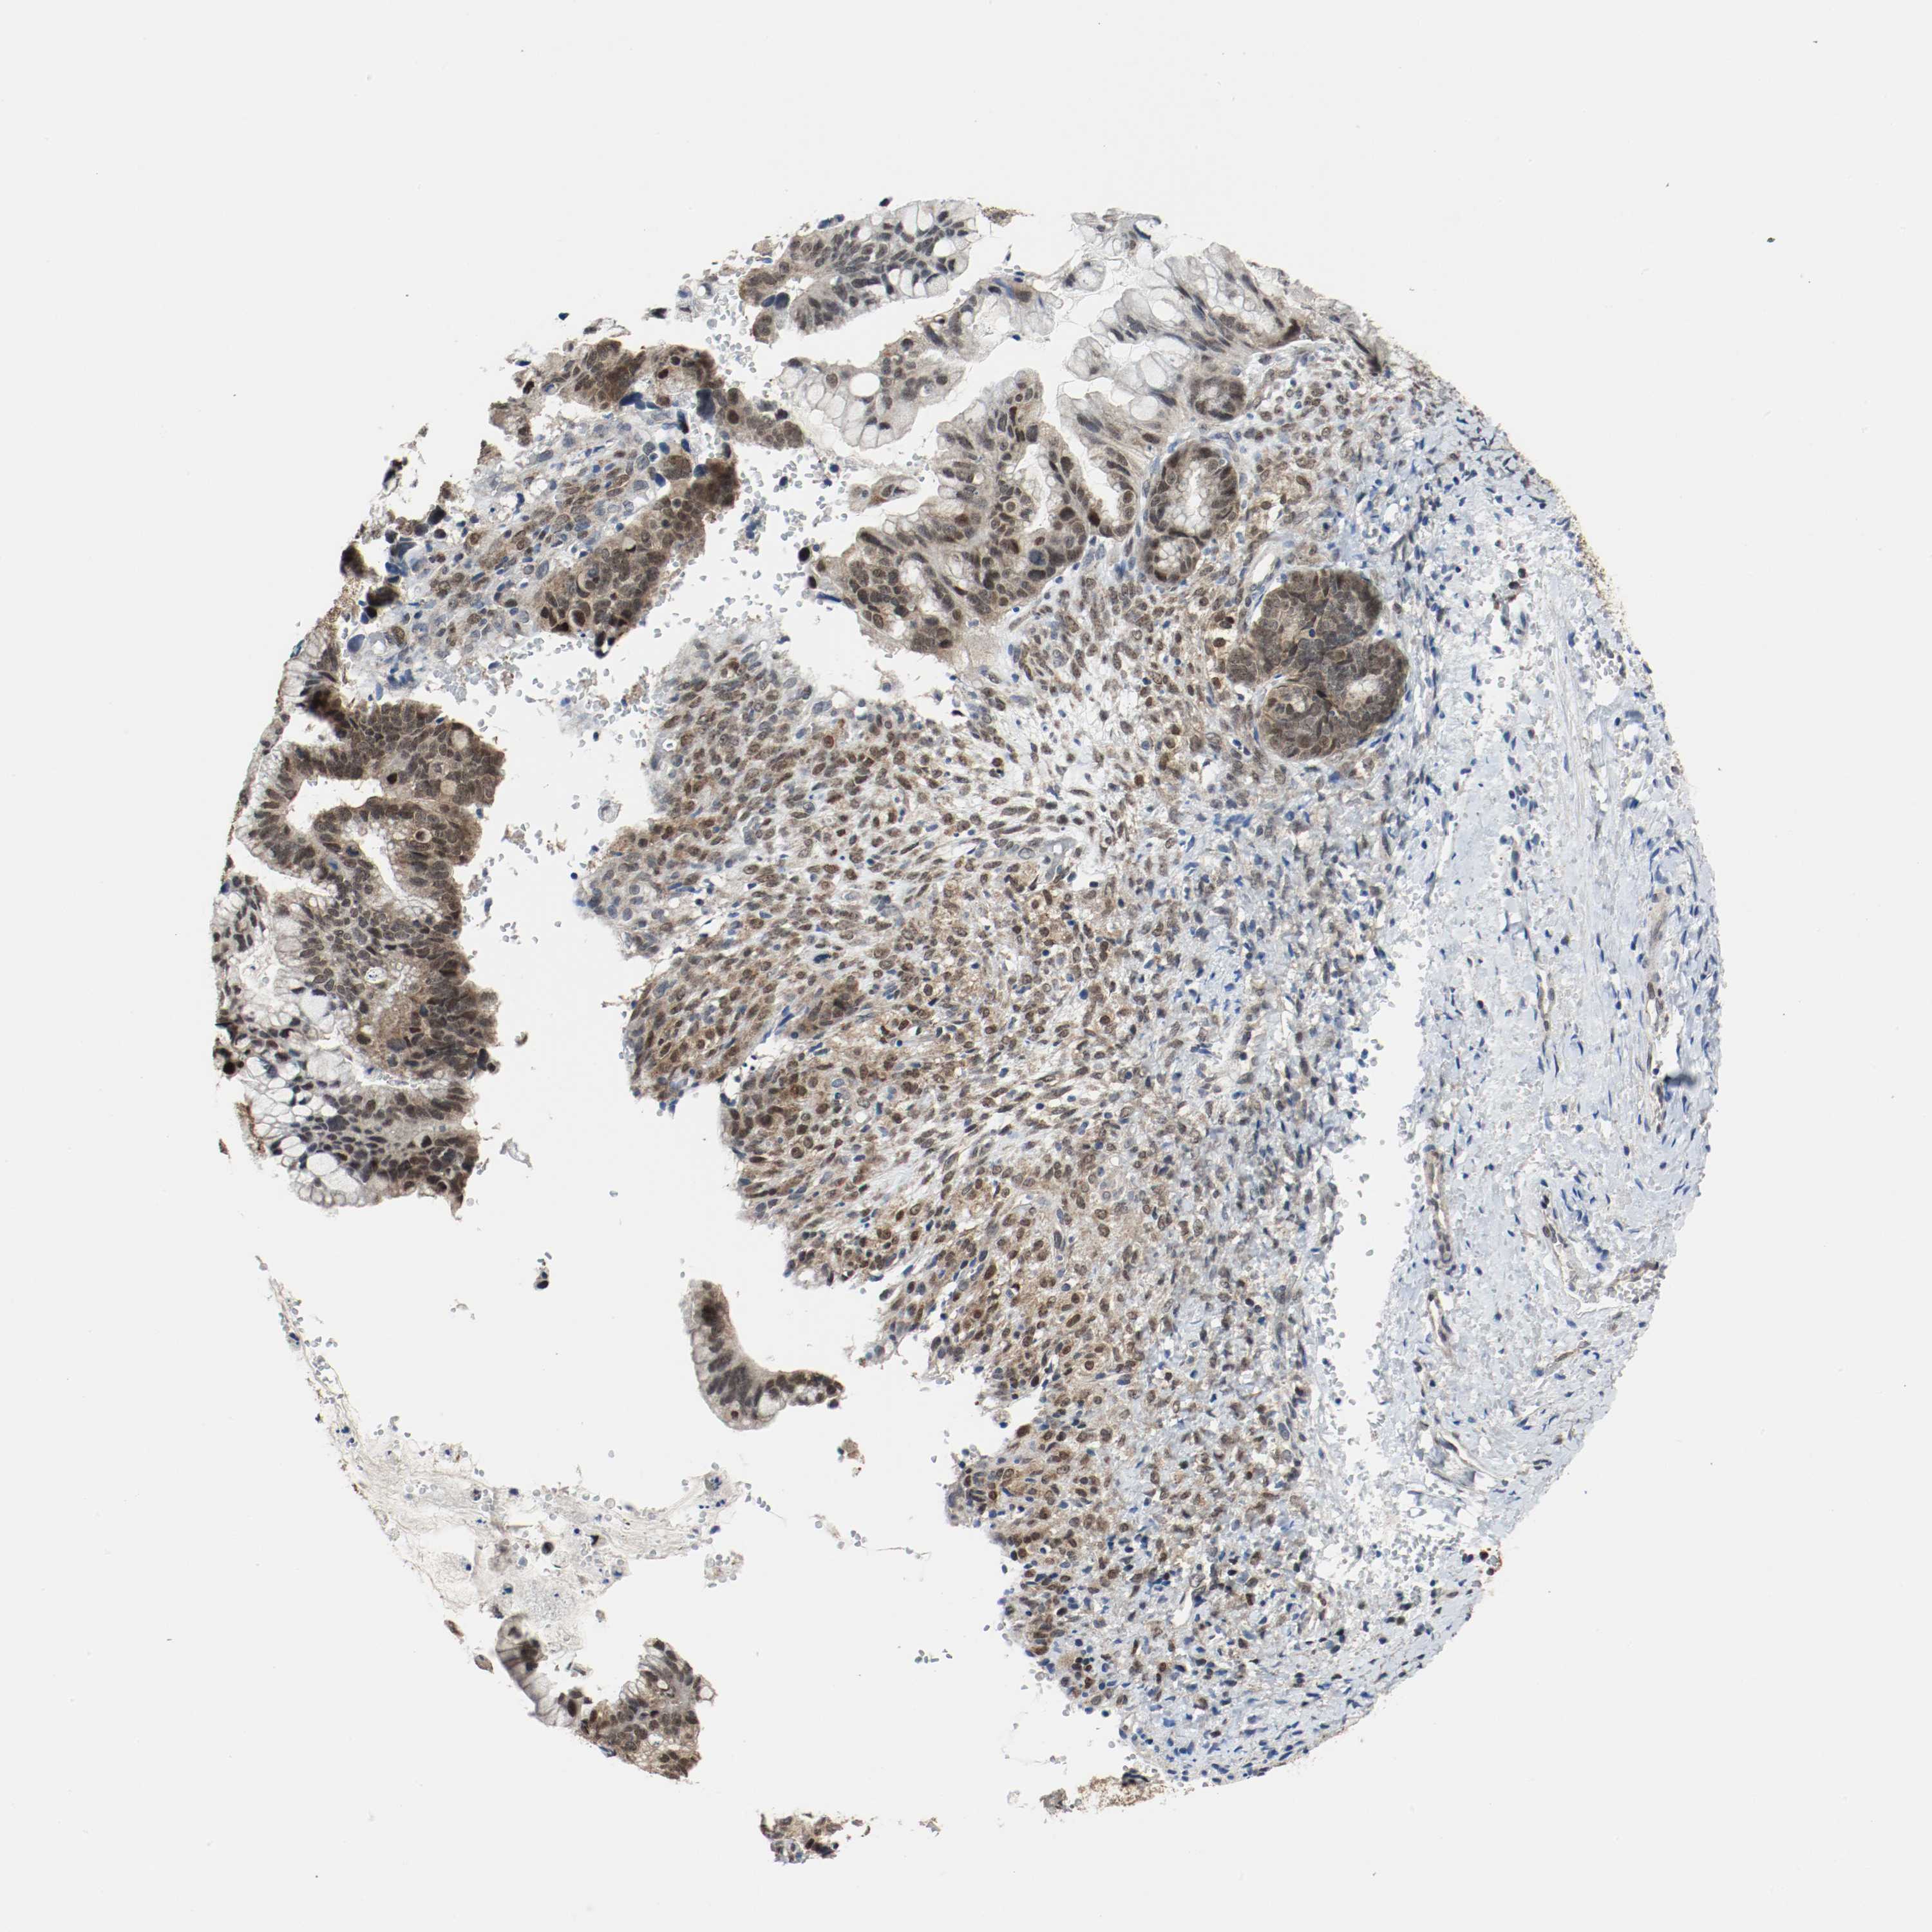

OVARIAN CANCER - Protein expressioni

A mouse-over function shows sample information and annotation data. Click on an image to view it in a full screen mode. Samples can be filtered based on level of antibody staining by selecting one or several of the following categories: high, medium, low and not detected. The assay and annotation is described here.

Note that samples used for immunohistochemistry by the Human Protein Atlas do not correspond to samples in the TCGA dataset.

Antibody stainingi

Antibody staining in the annotated cell types in the current human tissue is reported as not detected, low, medium, or high, based on conventional immunohistochemistry profiling in selected tissues. This score is based on the combination of the staining intensity and fraction of stained cells.

Each image is clickable and will lead to virtual microscopy that enables deeper exploration of all samples and also displays staining intensity scores, fraction scores and subcellular localization as well as patient and tissue information for each sample.

Antibody HPA043900

Antibody CAB004541

Staining

High

Medium

Low

Not detected

Intensity

Strong

Moderate

Weak

Negative

Quantity

>75%

75%-25%

<25%

None

Location

Nuclear

Cytoplasmic/membranous

Cytoplasmic/membranous,nuclear

Cystadenocarcinoma, serous, NOS

Carcinoma, NOS